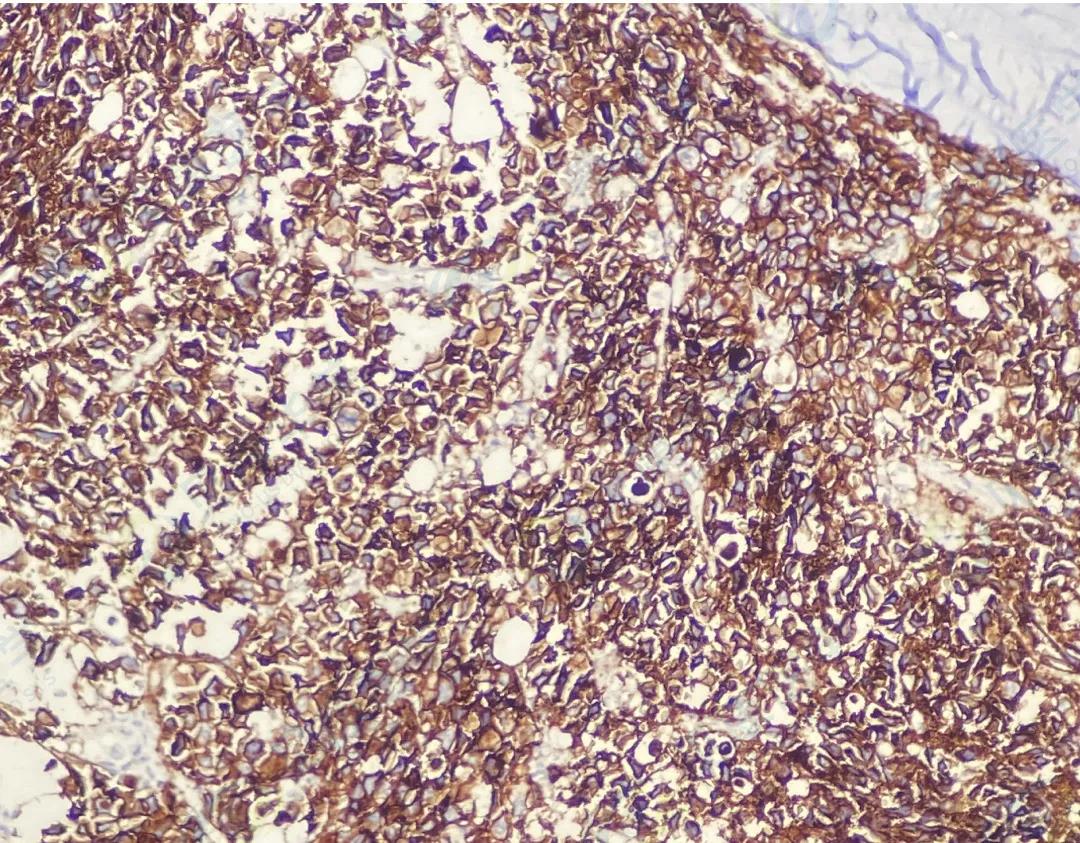

CD138

CD38

κ

λ